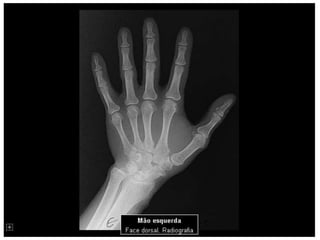

Esqueleto 1

Aula de anatomia acerca do esqueleto Humano 1